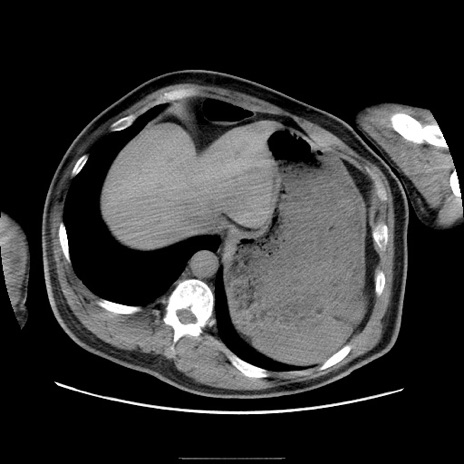

症例22(横断像)

【症例】50歳代男性

【主訴】腹痛

【現病歴】AVMからの被殻出血のため回復期リハ病棟入院中。 本日午後3時頃急に下腹部痛が出現した。

【既往歴】AVM、被殻出血、虫垂炎、高血圧

【身体所見】意識晴明、左半身不全麻痺、会話の理解は良好、36.5°C、腹部:膨隆、全体に板状硬、下腹部正中に圧痛点あり、反跳痛-、筋性防御不明、右下腹部にope scar

【データ】WBC 9400、CRP 0.06